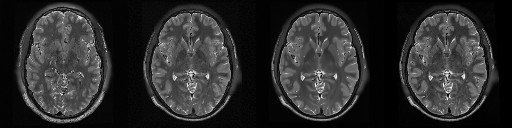

HCP T2w dataset

We utilize images from the publicly available Human Connectome Project (HCP) [51] T2-weighted (T2w) images dataset for the task of compressed sensing, which contains brain images from 47 patients. The HCP dataset includes cross-sectional images of the brain taken at different levels and angles.

Compressed sensing

We train a flow-based model from scratch on 10,000 randomly sampled images, utilizing the ncsnpp architecture [9] with minor adaptations for grayscale images. We employ compression rates , meaning . The measurement operator is given by a subsampled Fourier matrix, whose sign patterns are randomly selected. We evaluate our reconstruction algorithm’s performance on 200 randomly sampled test images.

We present the quantitative and qualitative results of compressed sensing in Tab. 1 and Fig. 4, respectively. As shown in Tab. 1, our method consistently achieves the best performance across varying compression rates . In Fig. 4, our method produces reconstructions that are more faithful to the original images, with fewer artifacts, leading to higher accuracy and clearer details.